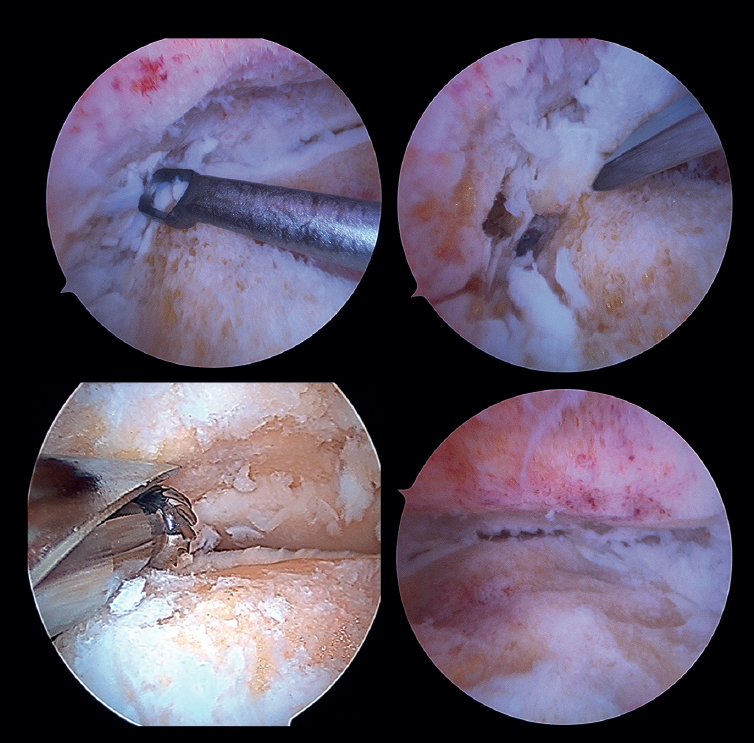

Preparation of the joint surfaces (Figure 4)

- In case of significant synovitis or arthrofibrosis, initial debridement is performed with a synoviotome allowing visualization of the joint.

- Large anterior osteophytes may be present, and their initial resection may require the use of a burr, curette or osteotome, taking care not to damage the anterior neurovascular structures. Resecting them from the start sometimes improves dorsiflexion of the talus and affords a better neutral position in the sagittal plane, as well as better visualization of the operating field.

It is useful to exchange viewing and working portals to access the full extent of the cartilage surfaces and to check complete resection.

The vaporizer is useful in cases of severe fibrotic impingement, which is characteristic of post-traumatic or second surgery scenarios, but again we should work as close to bone or joint space as possible, in order to avoid anterior tissue injury. - It is usually not necessary to use a distraction device to open the joint, since the joint space will progressively grow as the remaining joint cartilage is resected.

- Surgical curettage is performed, with chondral delamination and excision of the cartilage tissue until a viable cancellous bone bed is obtained. This can be done with or without motorized burr support, depending on each case.

- For preparation of the recesses, medial and lateral accessory portals can be used for drilling or curettage of both the medial aspect of the distal fibula and the lateral aspect of the medial malleolus.

- In cases of advanced syndesmotic lesions with marked widening, syndesmotic fusion is recommended, especially in cases of valgus arthropathy. The tibiofibular joint surface is typically prepared with one of the chosen shaver terminals.

- All residues are removed with specific instruments. Perforations can be added to obtain bleeding areas in the subchondral bone.

- Soft tissue release is performed, if necessary. This fundamentally applies to the deltoid ligament when there is a varus component in the joint disorder.

- In patients with major defects or poor bone stock, structural auto- or allografts are used on a case-by-case basis. We may require widening of the portals for their placement or mini-arthrotomies.

Figure 4. Preparation of the joint surfaces using different types of instruments: curettes, chisels or motorized drills. Final view after obtaining an optimal subchondral bed of the tibiotalar joint.